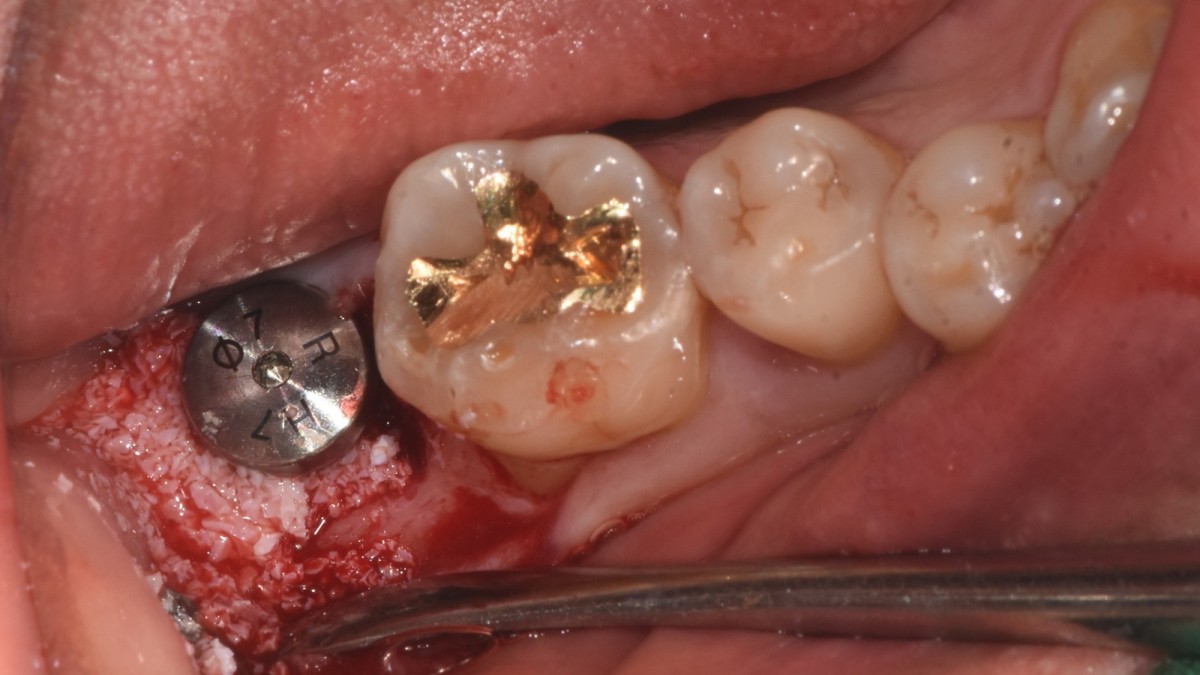

▲extraction

▲torque value after insertion

▲Arum Dentistry NB1 5*10